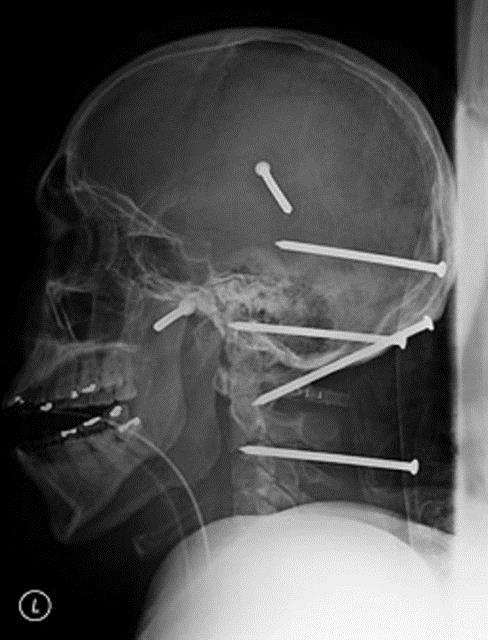

22. İsidro Mejia adlı Los Angeles'ta yaşayan bir inşaat işçisi geçirdiği kazayla ölümden döndü. Bir anlık dikkatsizlik sonucu makinadan fırlayan tam altı çivi kafatası ve boynuna saplandı.

İsidro Mejia adlı Los Angeles'ta yaşayan bir inşaat işçisi geçirdiği kazayla ölümden döndü. Bir anlık dikkatsizlik sonucu makinadan fırlayan tam altı çivi kafatası ve boynuna saplandı.